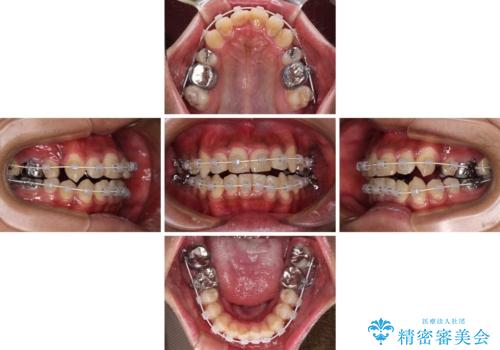

- 審美装置

自己管理が煩わしいとのことで、表側のワイヤー装置にて治療を進めて行くこととしました。

舌の突出癖により開咬となっていたため、突出癖改善のためのトレーニングをしっかりと行っていただき、予定の期間で無事に治療を終えることができました。